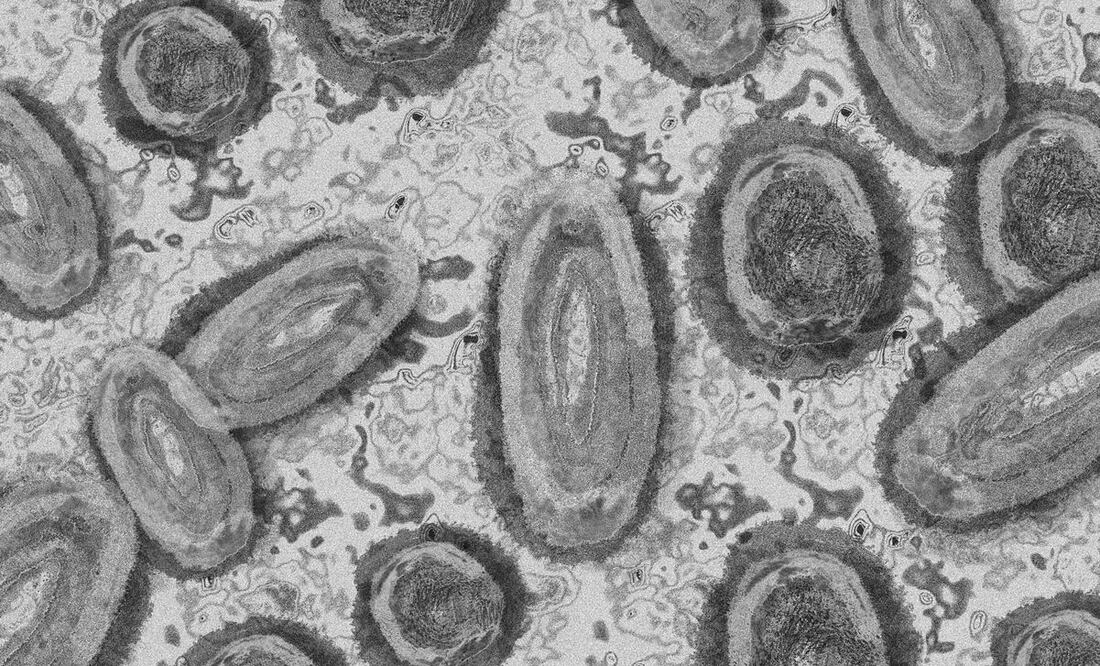

En la zona fronteriza de Coahuila con Estados Unidos, se detectaron dos casos de Viruela del Mono .

La Secretaría de Salud del estado confirmó a un hombre y una mujer contagiados con Viruela Símica, uno en el municipio de Acuña y otro en Piedras Negras.

El área de epidemiología de la dependencia tomó una muestra a un obrero de 24 años de Acuña que no presentó antecedente de viaje y registró síntomas como malestar general, aparición de máculas, pápulas y pústulas.

También confirmó el padecimiento en una mujer de 36 años, ama de casa, del municipio de Piedras Negras , quien tampoco presentó antecedente de viaje.

Ambos casos fueron detectados por la vigilancia epidemiológica que mantiene la Secretaría de Salud en los 38 municipios del estado.

Con estos dos se concentran en Coahuila 5 casos de Viruela del Mono, 2 en Saltillo, 2 en Acuña y uno en Piedras Negras.

Expertos señalan que los principales síntomas son ganglios linfáticos inflamados, sarpullido, granos o ampollas en la piel, fiebre, dolor de cabeza, escalofríos, cansancio, agotamiento físico, así como dolores musculares y de espalda.